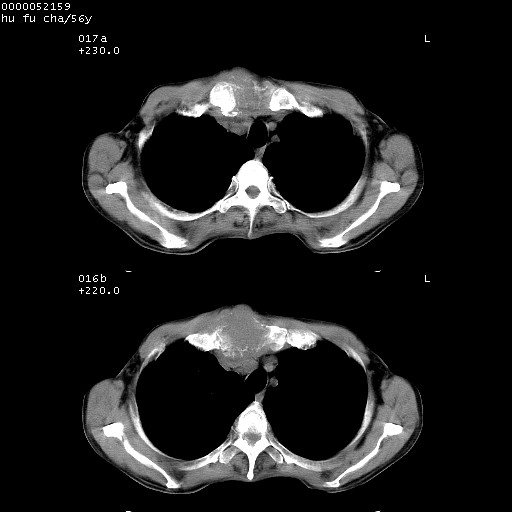

以下是引用zsl6918在2008-8-25 22:47:00的发言:[br]胸骨,胸椎及肋骨均可见多发转移表现,肝内低密度结节不除外转移。原发灶可能在右肺。双侧可见支扩表现。

以下是引用卜一在2008-8-26 8:02:00的发言:[br][br] 支持:肺癌并肺内,胸骨,胁骨,胸椎及肝内转移!另:左肺支气管扩张征伴感染! [br]

以下是引用zjzjr在2008-8-26 11:03:00的发言:[br]支持:肺癌并肺内,胸骨,胁骨,胸椎及肝内转移!另:左肺支气管扩张征伴感染!